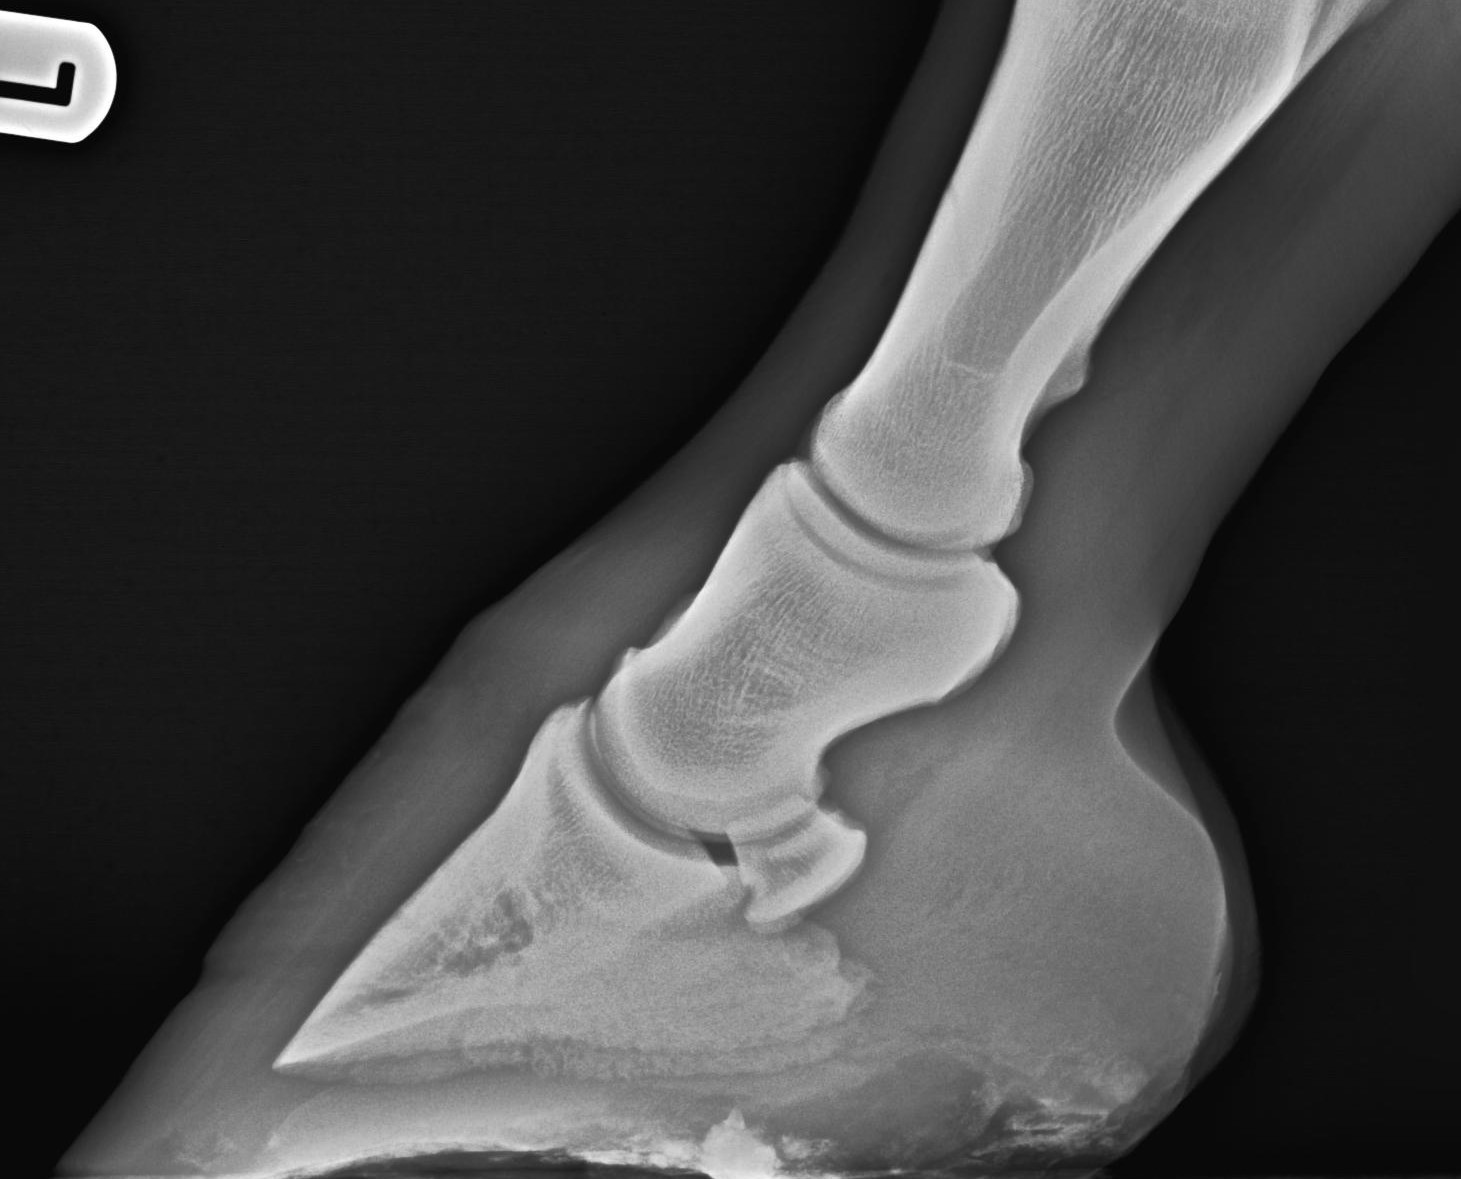

OCDTarsus